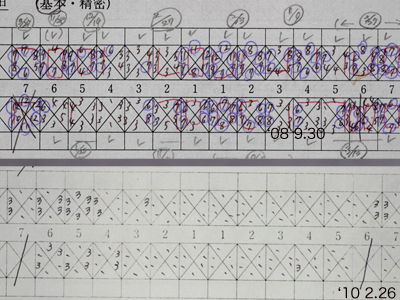

'08 9主治医の紹介で当院に来院されて以来、さすがに熱心にプラークコントロールに取り組んでいただきました。'08 9~'10 2のプロービングデプスの変化です。青は6mm以上、赤はBOPを示しています。

「PD6mm以上は歯周外科」というのがEBMだそうですが、EBMってのもあまりあてにならないことがわかります。そしてこの間の上下前歯部のレントゲン像の変化です。